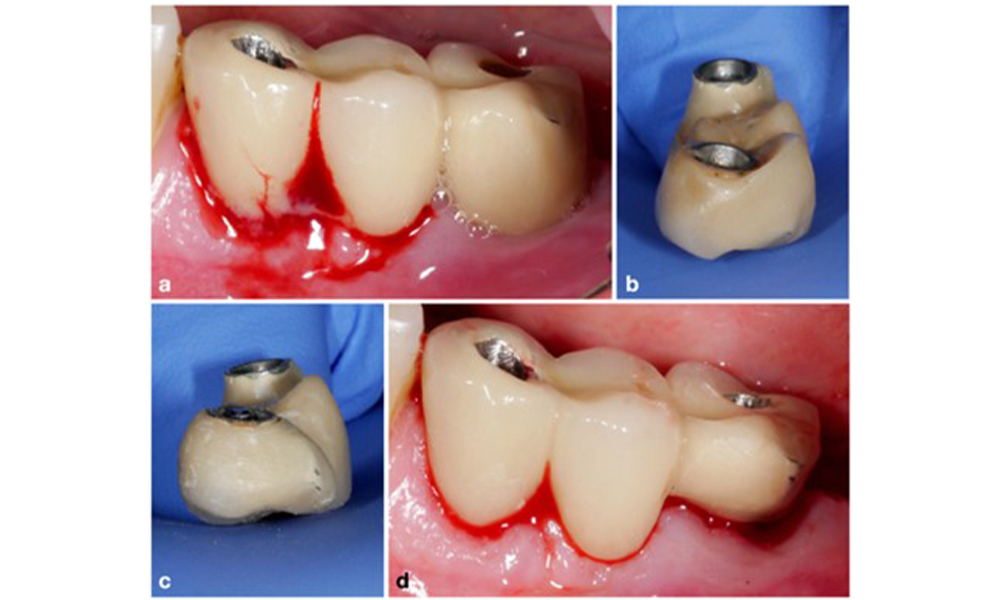

Peri-implantitis is identified by (1) signs of inflammation similar to mucositis, (2) radiographic evidence of bone loss after initial healing and (3) an increase in probing depth compared to measurements taken shortly after placing the prosthetic reconstruction (figure 2). In the absence of previous radiographs, radiographic bone level of ≥ 3 mm along with bleeding on probing and probing depths ≥ 6 mm, indicates peri‐implantitis.

Full-arch restoration with peri-implantitis of varying degrees at some implants. The implant in position 21 is severely affected with probing depths up to 9 mm (a), bleeding on probing, and suppuration from the peri-implant sulcus and a vestibular fistula (b–c); the radiograph shows approximately 50 % bone loss for the implant with peri-implantitis in position 21, while the implant in position 23 shows limited bone loss, corresponding approximately to what can be expected after initial healing for this type of implants (d).

Figure 2. Full-arch restoration with peri-implantitis of varying degrees at some implants. The implant in position 21 is severely affected with probing depths up to 9 mm (a), bleeding on probing, and suppuration from the peri-implant sulcus and a vestibular fistula (b–c); the radiograph shows approximately 50 % bone loss for the implant with peri-implantitis in position 21, while the implant in position 23 shows limited bone loss, corresponding approximately to what can be expected after initial healing for this type of implants (d).

The expected bone loss after initial healing attributed to marginal bone remodelling, varies based on factors such as the implant system or type. For instance, 1–2 mm bone loss is generally considered “normal” for bone level implants with an external connection (figure 2d, implant in position 23).